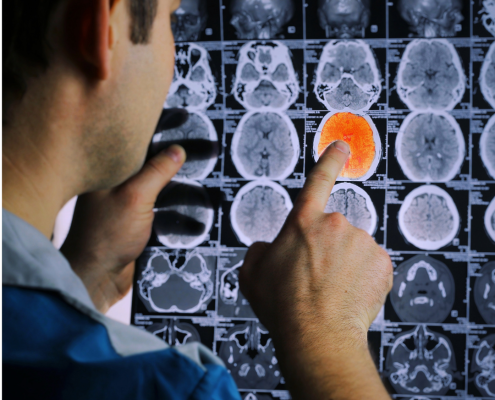

Summary of the International Scientific Meeting on Cerebral Venous Thrombosis 2023 (CVT Summit 2023)